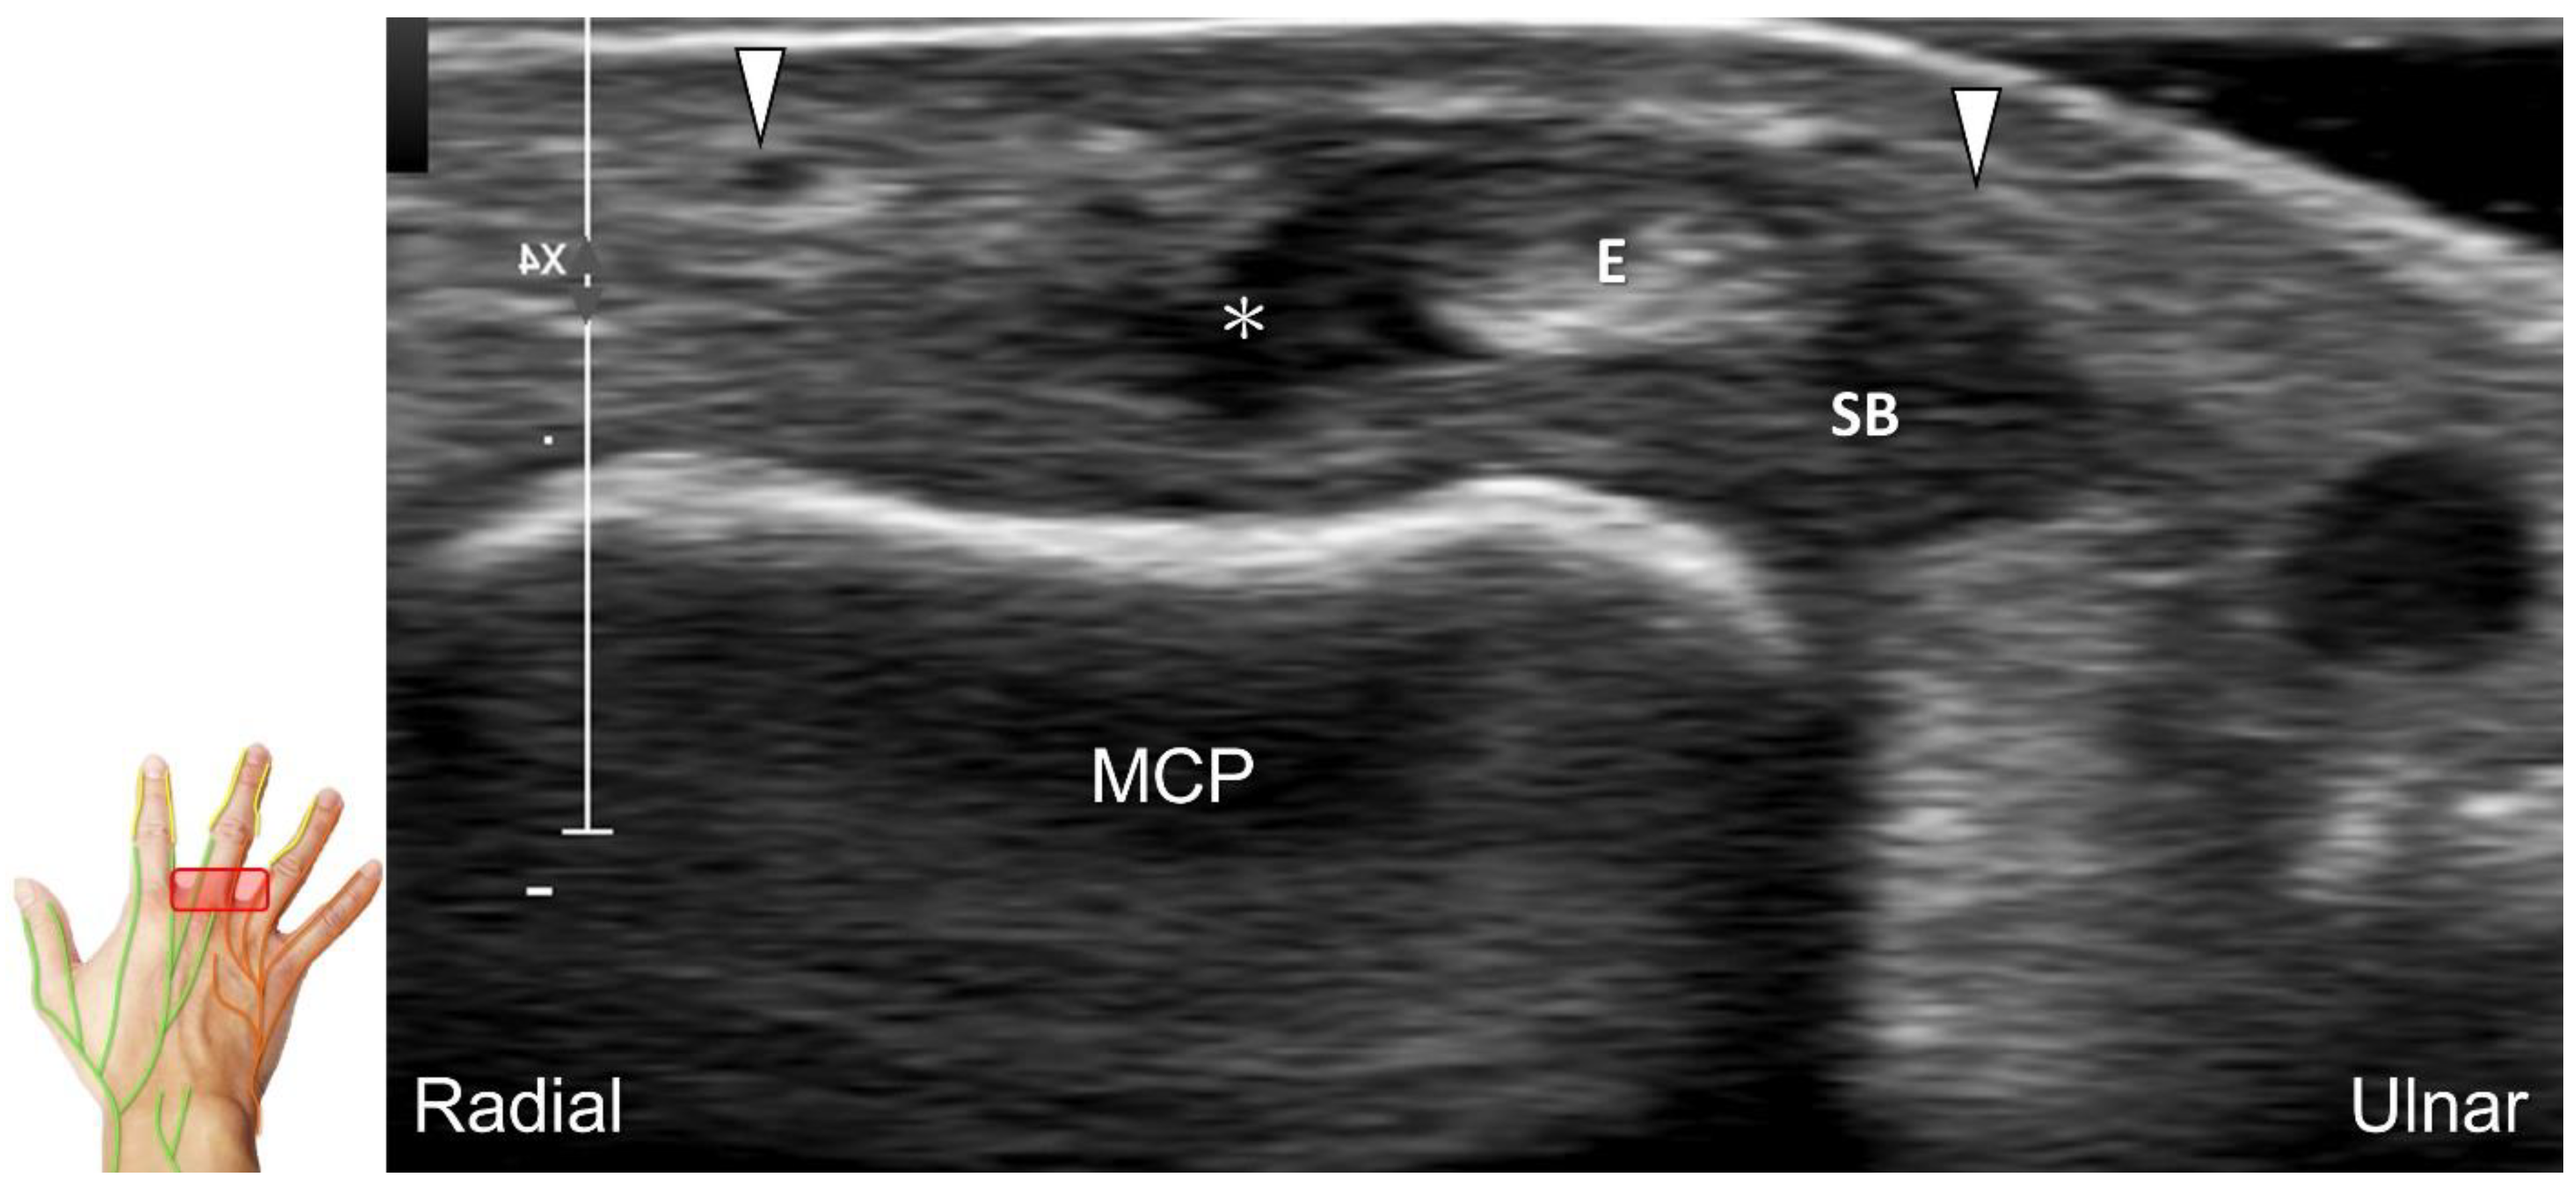

Scanning Technique

The transducer is positioned on the axial plane of the dorsal metacarpal joint in the target digit. The dorsal proper digital nerves can be found on either side of the sagittal band (Figure 33A). The transducer is moved proximally and the dorsal common digital nerves can be observed superficial to the extensor (usually the extensor digitorum proprius) tendons (Figure 33B). By returning to the level of the sagittal band and moving the transducer distally, the dorsal proper digital nerves can be seen superficial to and alongside the central slip of the finger extensor tendon (Figure 33C). Alternatively, moving the transducer distally toward the proximal phalanx of the first to the radial aspect of the fourth phalanx allows observation of the nerve fascicles of the palmar proper digital nerve originating from the median nerve (Figure 33D).

Clinical Implication

Injuries to the dorsal common digital nerve typically occur in the workplace as a result of cutting or crushing. However, the nerve can also sustain damage due to various other factors such as fracture, ganglia, tenosynovitis, tumor (Figure 34), foreign objects, or boxing, which may cause contusion over the first knuckles (Figure 35).

US imaging may reveal a neuroma in cases where patients report chronic allodynia and/or tingling sensation in the affected digit (Figure 36). To perform hydrodissection, the in-plane approach can be utilized in the nerve’s short axis after identifying the extensor digitorum tendons and the dorsal metacarpal arteries (Figure 37).

Figure 33. Sonographic imaging of the dorsal common digital nerve on the metacarpal bone (A), toward the metacarpal head (B). Dorsal proper digital nerves on the proximal phalanx (C), and the terminal nerve originating from the palmar proper digital nerve on the distal phalanx of third finger (D). Arrowheads: dorsal common digital nerve; arrows: palmar proper digital nerve. MCP: metacarpal bone; SB: sagittal band; E: extensor tendon; Cs: central slip; PP: proximal phalanx; T: terminal band; DP: distal phalanx; DIO, dorsal interosseous muscle.

Figure 35. Sonographic imaging reveals irritation of the ulnar aspect of the dorsal common digital nerve due to extensor tendon subluxation resulting from a tear in the sagittal band. Arrowheads: dorsal common digital nerve; asterisk: tear of the sagittal band. SB: sagittal band; E: extensor tendon; MCP: metacarpal bone.